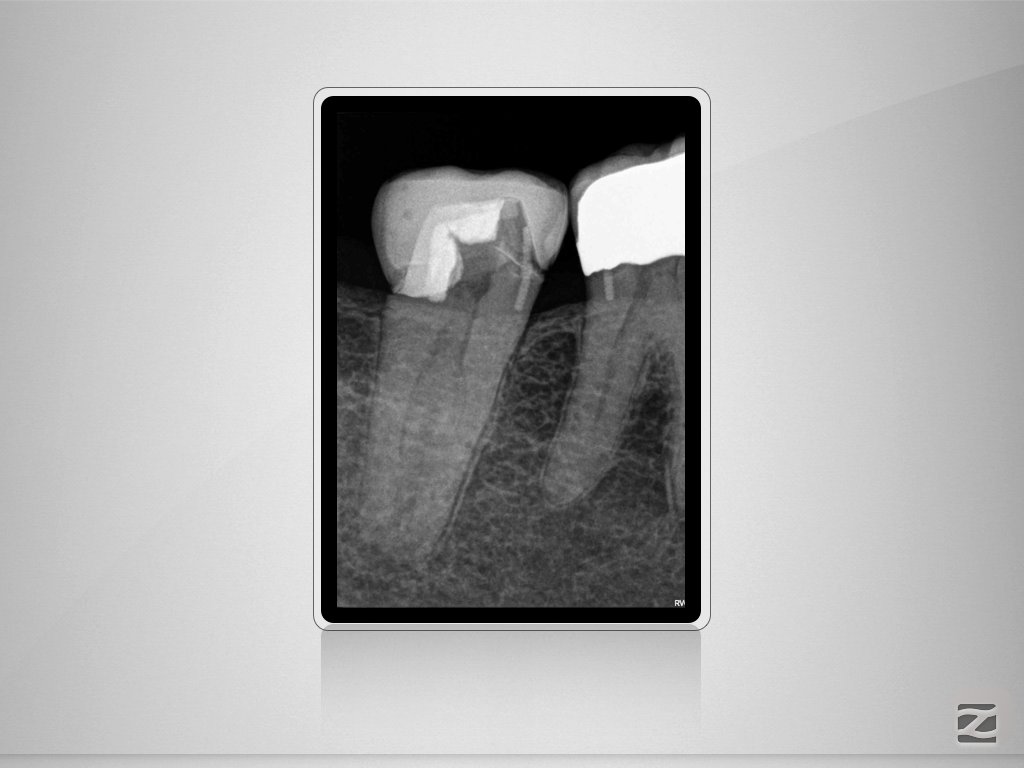

47d-001

„C“ ja – „C“ nein